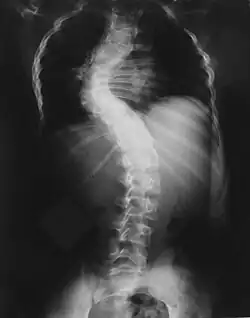

- powikłania ortopedyczne: dysplazje i deformacje kostne, zwłaszcza skolioza odcinka piersiowego kręgosłupa, dysplazja skrzydeł większych kości klinowej, deformacje kości strzałkowej i piszczelowej, złamania patologiczne z tendencją do tworzenia stawów rzekomych (25%)